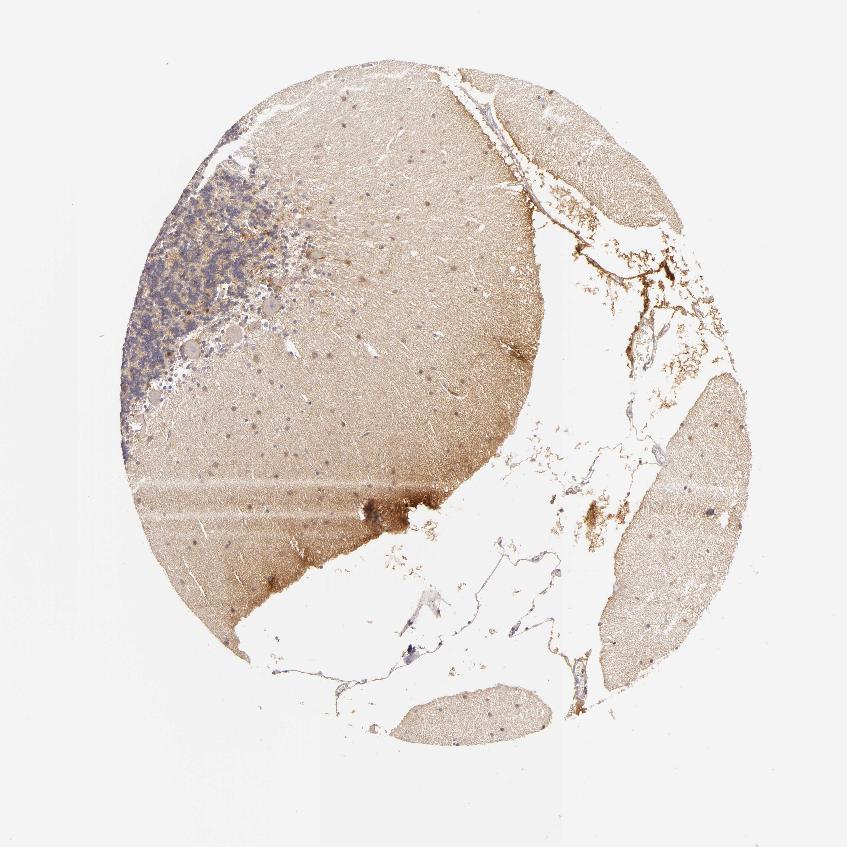

CEREBELLUM - Antibody stainingi

Antibody staining in the annotated cell types in the current human tissue is reported as not detected, low, medium, or high, based on conventional immunohistochemistry profiling in selected tissues. This score is based on the combination of the staining intensity and fraction of stained cells.

Each image is clickable and will lead to virtual microscopy that enables deeper exploration of all samples and also displays staining intensity scores, fraction scores and subcellular localization as well as patient and tissue information for each sample.

Antibody CAB002159

Purkinje cells Low

Cells in granular layer Low

Cells in molecular layer Low